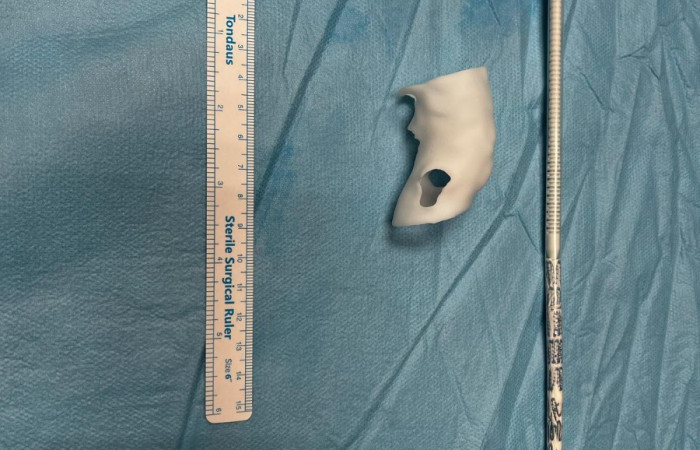

Widoczna na zdjęciach matryca aorty wydrukowana została z żywicy fotopolimerowej, która przeszła proces sterylizacji plazmowej. Użycie technologii 3D umożliwiło indywidualne dostosowanie implantowanego stentgraftu do anatomicznych warunków odejścia naczyń trzewnych od aorty, co z kolei pozwoliło na zakwalifikowanie chorego do małoinwazyjnej procedury zaopatrzenia tętniaka aorty piersiowo brzusznej metodą wewnątrznaczyniową w trybie przyspieszonym.

To kolejne rozwiązanie użycia nowych technologii, które pozwala na znacznie szybszy powrót do zdrowia Pacjenta i opuszczenie szpitala już po kilku dniach.